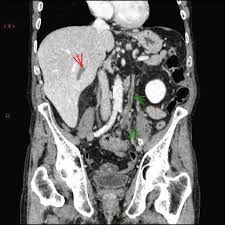

Chiasmata -mə-tə or chiasmas also chiasms 1. Esophageal varices are extremely dilated sub-mucosal veins in the lower third of the esophagus. Located in metro Denver northern Colorado and western Nebraska serving all of the Front Range our team consists of board-certified and fellowship-trained interventional radiologists. This results in hepatic congestion similar to Budd-Chiari syndrome and post-sinusoidal portal hypertension. The patients condition should be monitored throughout the procedure. They are most often a consequence of portal hypertension commonly due to cirrhosis. Toxic injury to liver sinusoids causes sloughing of endothelial cells that embolize to hepatic venules and cause eventual fibrosis of the venules. Coin in the Esophagus. There is no clear consensus regarding the number of occluded veins some authors claim that there should be at least one occluded hepatic vein 7 others state that there are no significant.

Carcinoma of the Colon. Budd-Chiari syndrome a blockage in one or more veins that carry blood from the liver back to the heart. And coumarin skin necrosis adrenal gland hemorrhage and infarction. Toxic injury to liver sinusoids causes sloughing of endothelial cells that embolize to hepatic venules and cause eventual fibrosis of the venules. Chiari malformation CM is a structural defect in the cerebellum characterized by a downward displacement of one or both cerebellar tonsils through the foramen magnum the opening at the base of the skull. Embolism and thrombosis of. La présence dune ou plusieurs affections prothrombotiques est fréquente La prise en charge repose sur un traitement anticoagulant précoce le traitement de l.